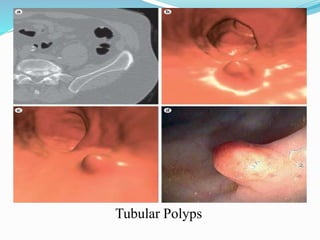

This document discusses colorectal polyps. It defines polyps and describes their types, including neoplastic and non-neoplastic polyps. It discusses adenomatous polyps in depth, noting their malignant potential increases with size over 1cm and villous architecture. Radiological diagnostic methods for polyps including single and double contrast barium enema and CT colonography are explained. The document provides an overview of polyp pathogenesis and genetic syndromes like FAP that increase cancer risk.